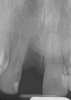

Case 3. TRAUMA: SINGLE Central INCISOR-GUIDED Smile

A 23-year-old man reported to the dental practice on January 3. Apparently, while on vacation and celebrating the New Year, the patient experienced a loss of equilibrium and found himself horizontal in the crosswalk. When surveying the damages, his friends noticed he was missing tooth No. 8. Those who were involved were not able to find the missing maxillary central incisor. The young man was eventually seen about 3 days after the trauma. A CBCT radiograph, study models, and photographs were collected, and teeth Nos. 6 through 10 were immobilized with composite and 20 x 20 orthodontic wire (Figure 14). The CBCT and photos were emailed to the dental laboratory, and the analog intraoral impression with a centric occlusion bite registration was sent via ground transportation. Due to the nature of the trauma, the laboratory and the author expeditiously converted the analog diagnostics and merged all the patient's data sets to develop the plan. Based on the 3D data sets, the laboratory and the dentist were able to accurately assess the volume of bone and soft tissue remaining after the trauma. The volume was still intact and soft tissue was plentiful (Figure 15 and Figure 16).

Fig 15. Surgery was planned for 10 days after the trauma incident.

Figure 15

Fig 16. Preoperative periapical radiograph on the day of surgery.

Figure 16